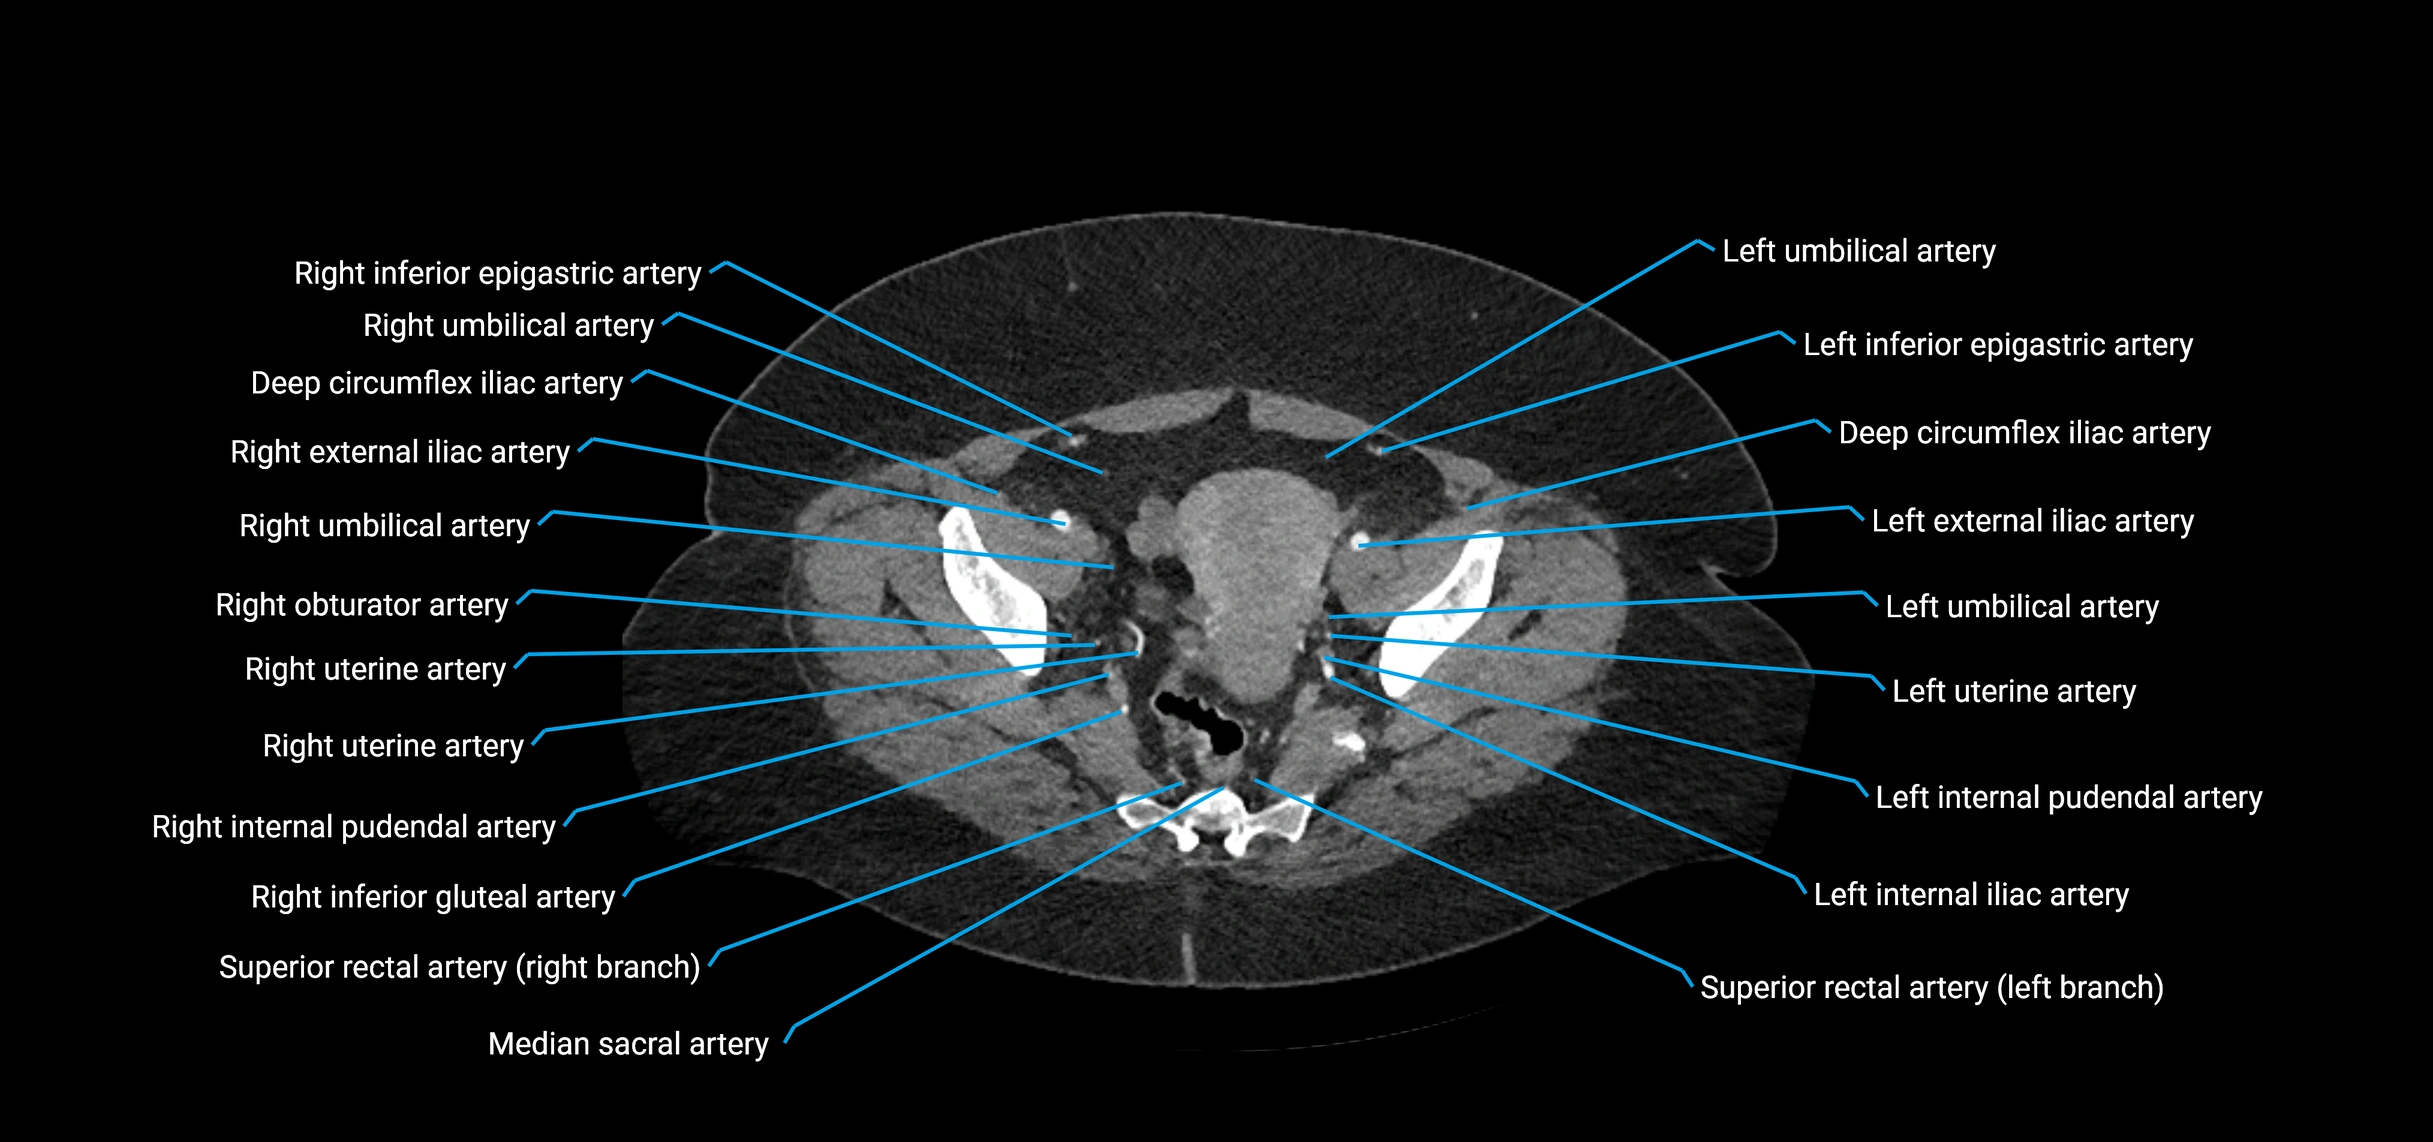

Contrast-enhanced CT (CTA):

• Gold standard for abdominal aortic imaging

• Provides excellent detail of lumen, wall, aneurysm, thrombus, and branch vessels

• Multiplanar and 3D reconstructions help in aneurysm measurement, stent graft planning, and dissection evaluation